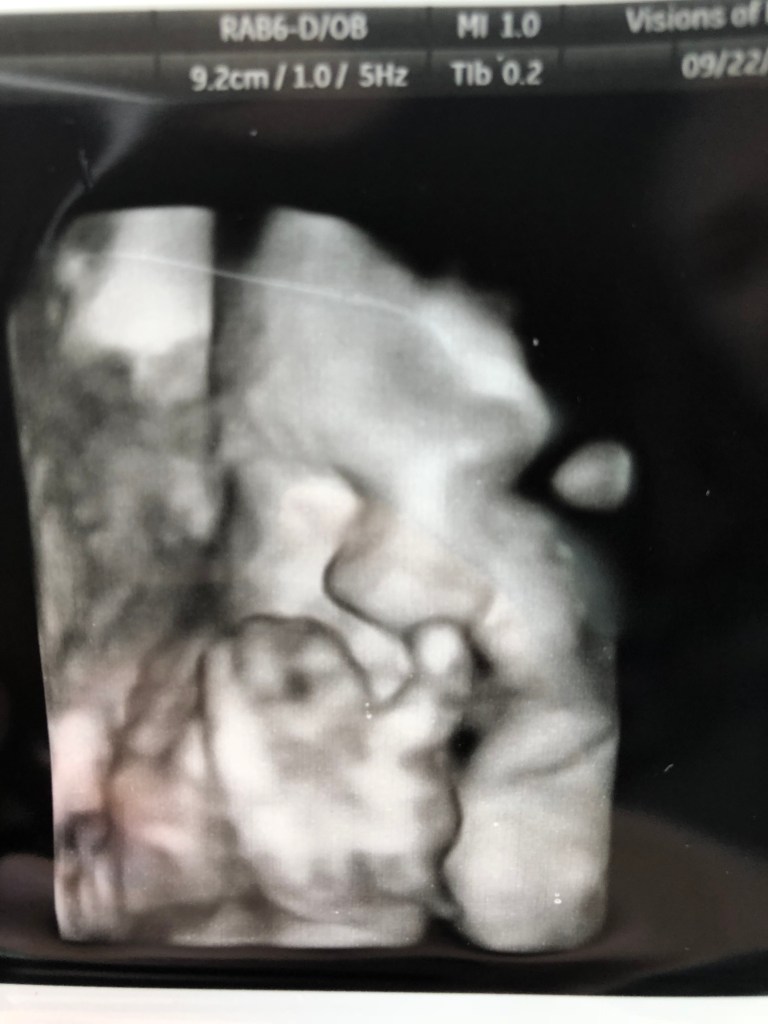

When I found out I was pregnant, I was, at first, beyond scared. I had just started nursing school and I was working towards finding my “why”. Garrett never failed to promise me that it was going to be wonderful, and that it was a blessing. I quickly came around, and I was so excited to be a mom. I began imagining a nursery, what our baby would look like, who they would become, and all the things that come with new mom territory. So along came the “morning sickness” which was truly all dang day sickness. That didn’t go away until I was like 34 weeks pregnant, so that was really fun. NOT. Anyway. We had to wait F O R E V E R, so it seemed, for our first appointment! I was 10 weeks when we had our first appointment and got to see the little peanut in my stomach and hear a little heartbeat. It was the cutest and best day. We opted to do a blood test to find out the gender at 12 weeks!